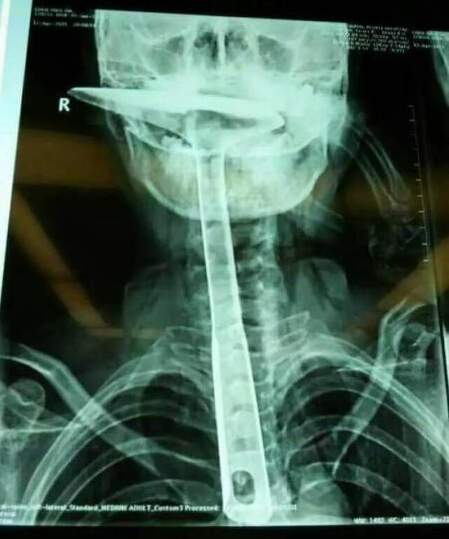

炒菜用的鍋鏟長達30公分,活生生插進自己的食道。

南都訊 記者肖佩佩 炒菜用的鍋鏟,長達30公分,活生生插進自己的食道,只剩下鏟勺露在嘴巴外面,整個食道嚴重受損。醫生都不禁感嘆:“這真的是50年難遇的病例。”

陳女士被緊急送到東莞第五人民醫院,醫生拍片顯示,整個鐵鍋鏟把手已經在胸里了,病情嚴重。當晚,陳女士就被轉到了康華醫院。“患者來院時,嘴巴里只剩一個鍋鏟鏟勺露在外面,整個鍋鏟手柄已經被插入到食道里了。”康華醫院胸外科接診醫生陳羽彪說,檢查發現,鍋鏟總長大概30公分長,手柄直徑約2.5公分,整個已經插入食道,食道表皮粘膜損傷嚴重,且被捅破了一個洞,“而且,手柄已嚴重擠壓到了肺部,導致右肺部已無法正常擴張。”

“這樣的病例,不說100年難遇,也是50年難遇了。”康華醫院胸外科主任肖樸說,患者情況嚴重,醫院立即組織專家會診。“胸腔全是大血管,一旦拔出就有可能大出血,危及性命。”當天晚上11點,醫生決定為患者進行一期手術即食道擴置手術,“我們先將鍋鏟從食道里面拔出來,由于胸位食道受損嚴重,只能切除了。”

醫生介紹,食道總長約25公分,患者切除了20公分,切除部分主要集中在胸位段,食道只保留到了頸部,只能露出來進行醫學處理,吞咽口水、積液進行人工及時清理更換。”